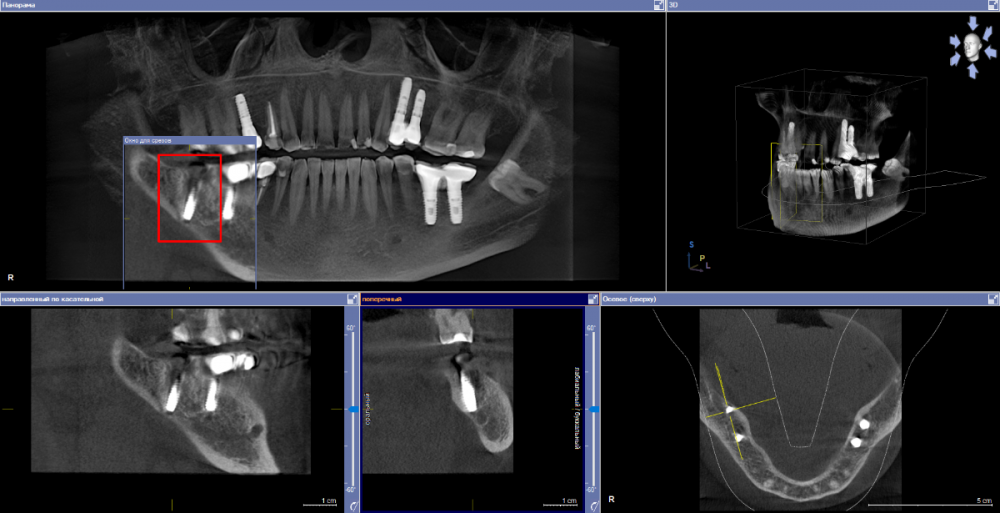

se77777 Опубликовано 3 апреля, 2023 Автор Поделиться Опубликовано 3 апреля, 2023 (изменено) Пожалуйста, дайте ссылку, как правильно выставлять срезы. Изменено 3 апреля, 2023 пользователем se77777 Загрузка изображений Ссылка на комментарий

se77777 Опубликовано 4 апреля, 2023 Автор Поделиться Опубликовано 4 апреля, 2023 Может быть, еще как-то иначе вывести срезы? Ссылка на комментарий

АнтонТЛТ Опубликовано 4 апреля, 2023 Поделиться Опубликовано 4 апреля, 2023 У нижних двух окошек есть ползунки слева. Оси нужно выставить параллельно имплантату 1 Ссылка на комментарий